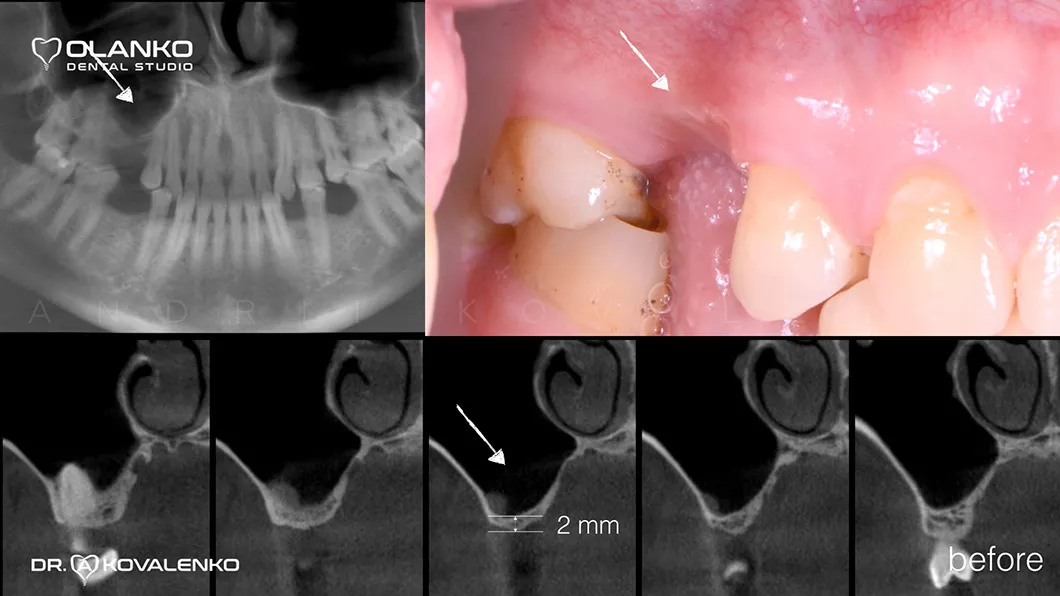

Атрофия — это прогрессирующая убыль костной ткани, которая сопровождается уменьшением ширины и высоты альвеолярного гребня. Развивается после удаления зуба и является самым распространённым препятствием для установки зубного имплантата.

Специалисты Olanko dental studio (Оланко) г. Бровары рекомендуют проводить операцию по установке зубного имплантата в максимально ранний период после удаления проблемного зуба (от 3 до 6 месяцев), или использовать методику имплантации одномоментно с удалением зуба тогда, когда есть условия для проведения такой операции. Но если убыль костной ткани уже наступила, мы прибегаем к использованию хирургического восстановления объёмов костной ткани — костной пластике.

Костная пластика – это хирургическая операция, которая позволяет восстановить объём челюстной кости, для будущей зубной имплантации, с помощью костной ткани, взятой в донорских зонах у пациента, или искусственного костнопластического материала, а также смеси костных материалов.

Операция костной пластики может выполнятся как самостоятельно, так и совместно с установкой зубного имплантата.

Специалисты Olanko dental studio (Оланко) г. Бровары, при выборе метода костной пластики, проводят детальный анализ компьютерной томографии и виртуально расставляют положение будущих имплантатов в специальном программном обеспечении IMPLANT STUDIO 3Shape.